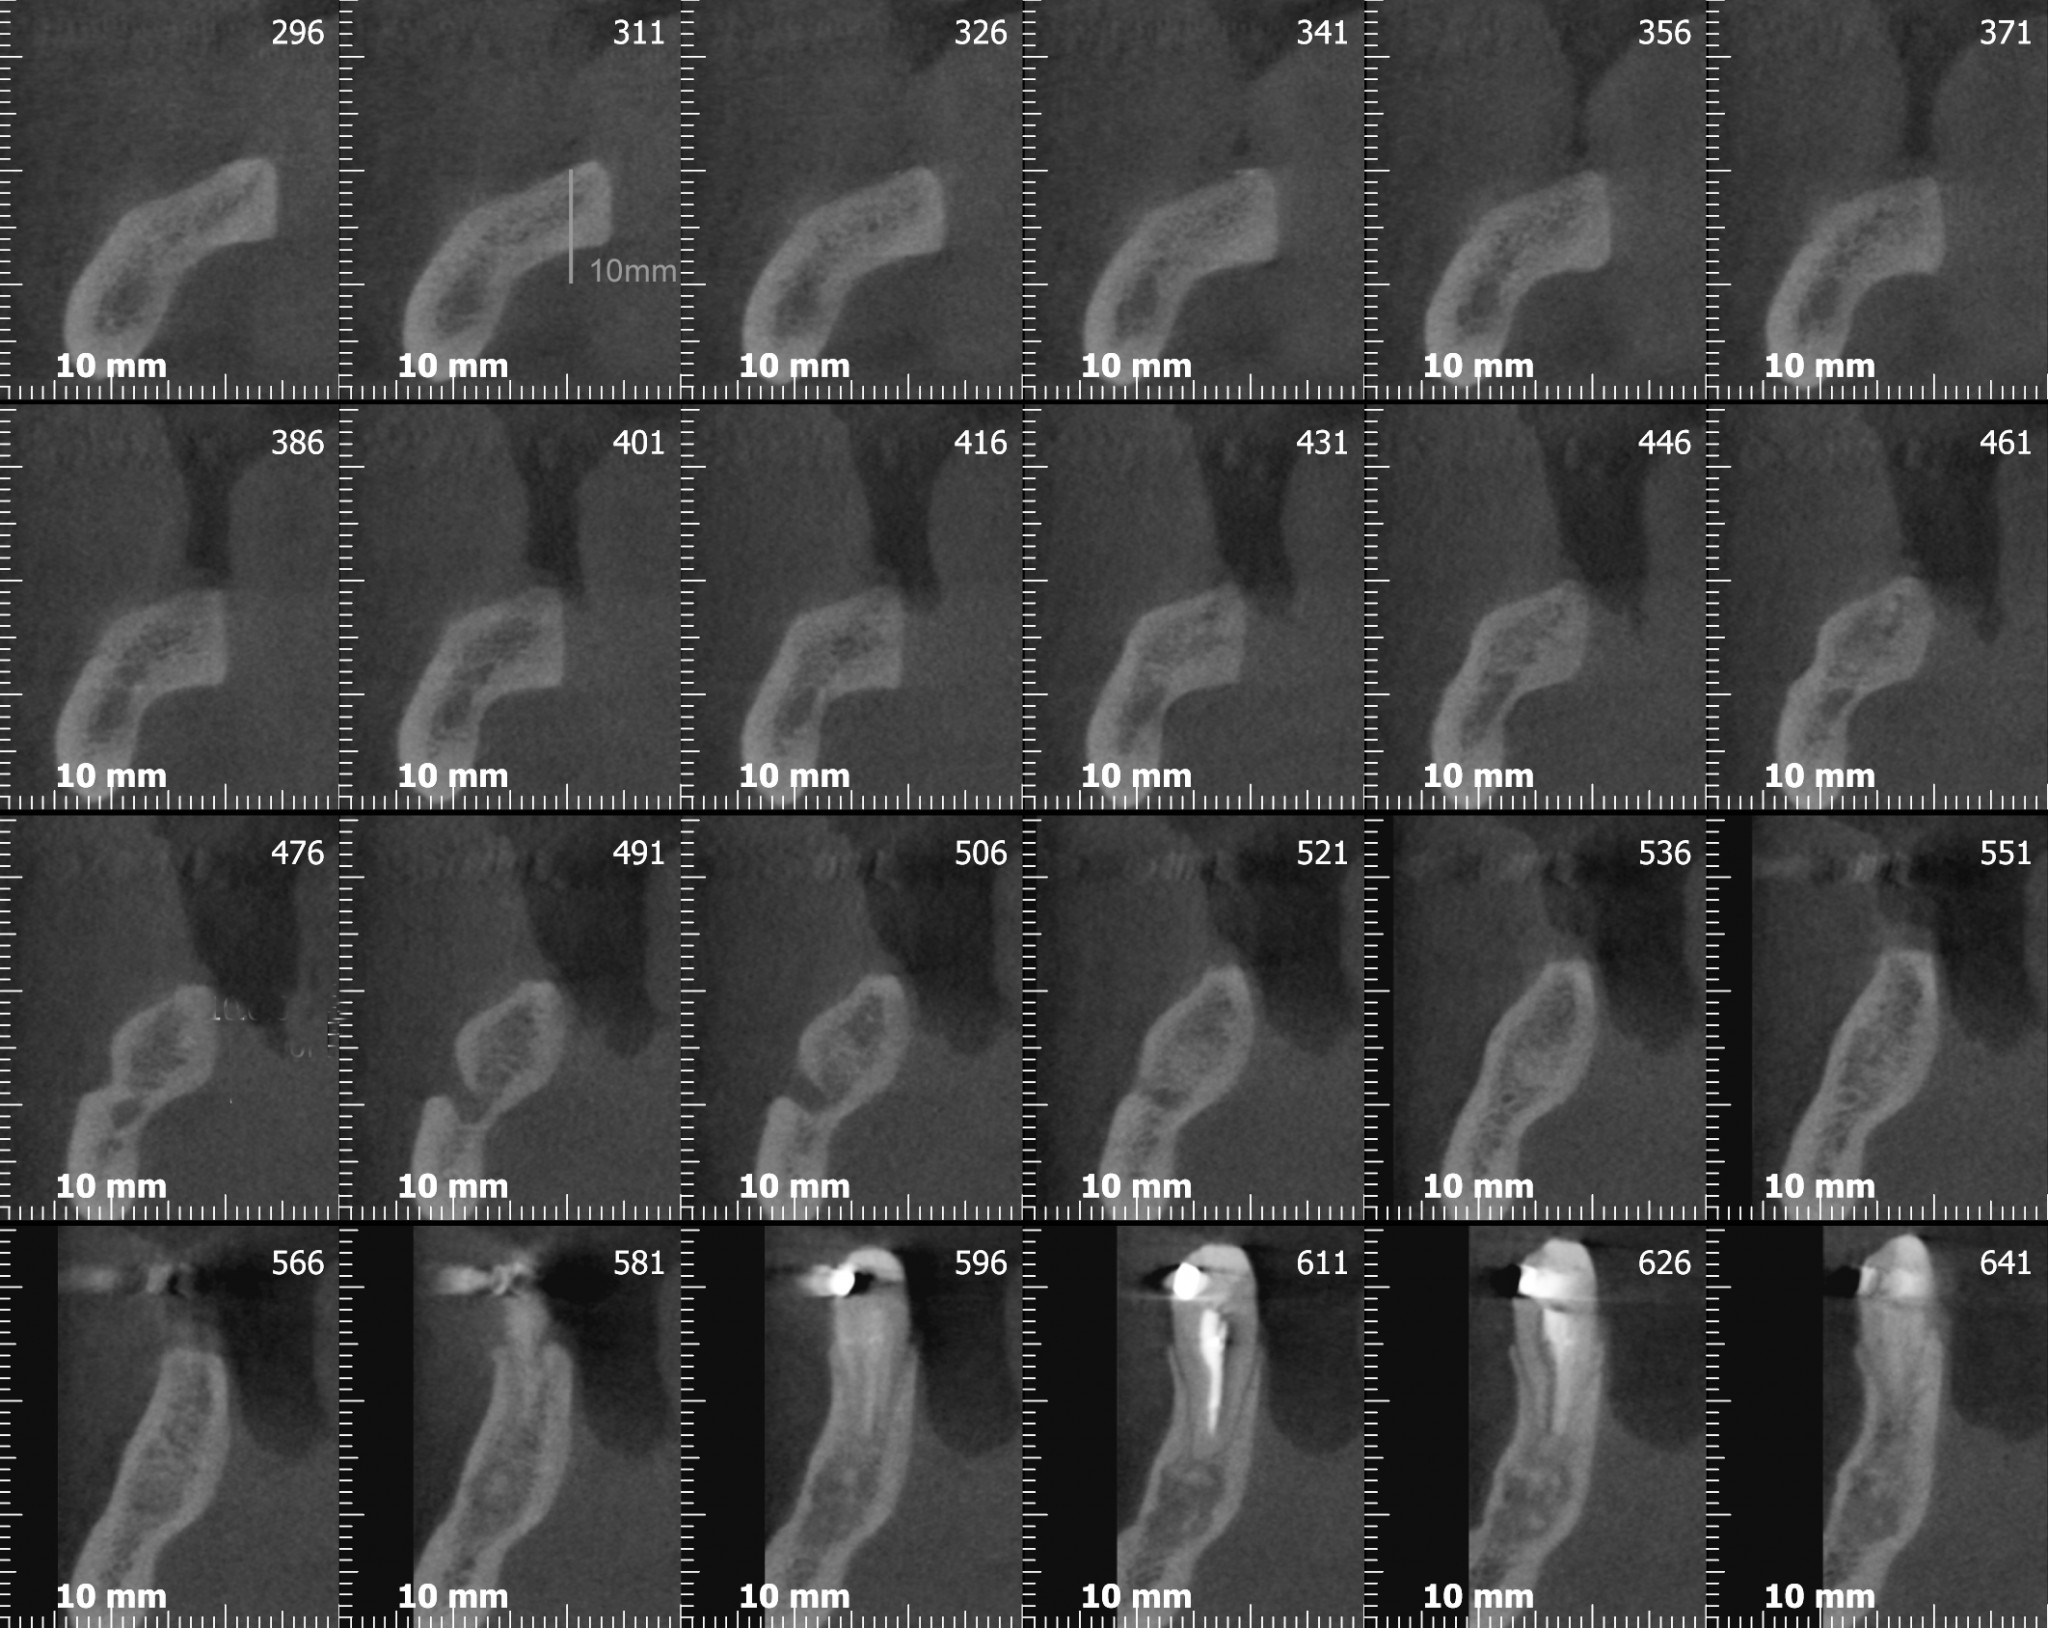

Ora guarda attentamente…….

….Ancora….

Cosa vedi? Ok, una bella atrofia orizzontale, associata ad una modesta atrofia verticale. Come possiamo trattare una atrofia verticale associata ad una orizzontale? (rimanendo all’interno dell’evidence based medicine per carità!)

Avevi notato questo? Dai tagli della cone-beam si nota chiaramente una variante anatomica abbastanza importante: un foro mentoniero accessorio posizionato più o meno a metà tra la cresta e il foro primario, diciamo circa 7 mm apicalmente alla cresta, dal quale emerge un ramo di diametro rilevante del nervo alveolare inferiore. Chissà a quale parte del mento o del labbro porta le sensibilità quel piccolo ramo!? Diciamo che per mantenere immacolato il mio palmares medico legale preferisco non scoprirlo!

Infatti ben poco sotto il livello della cresta compare l’infame…

Se lo lasciamo lì ovviamente non possiamo ricostruire un bel niente, ti faccio allora vedere come ho risolto io la situazione, ma a parte il tecnicismo chirurgico spero che il messaggio ti sia chiaro: